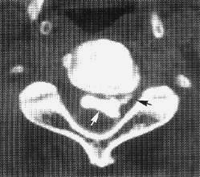

CT、MRI檢查:鞘膜囊和骨性椎二者大小比例改變,鞘膜囊和神經根受壓,硬膜外脂肪消失或減少,關節突肥大使側隱窩和椎管變窄,三葉狀椎管,弓間韌帶、後縱韌帶肥厚。